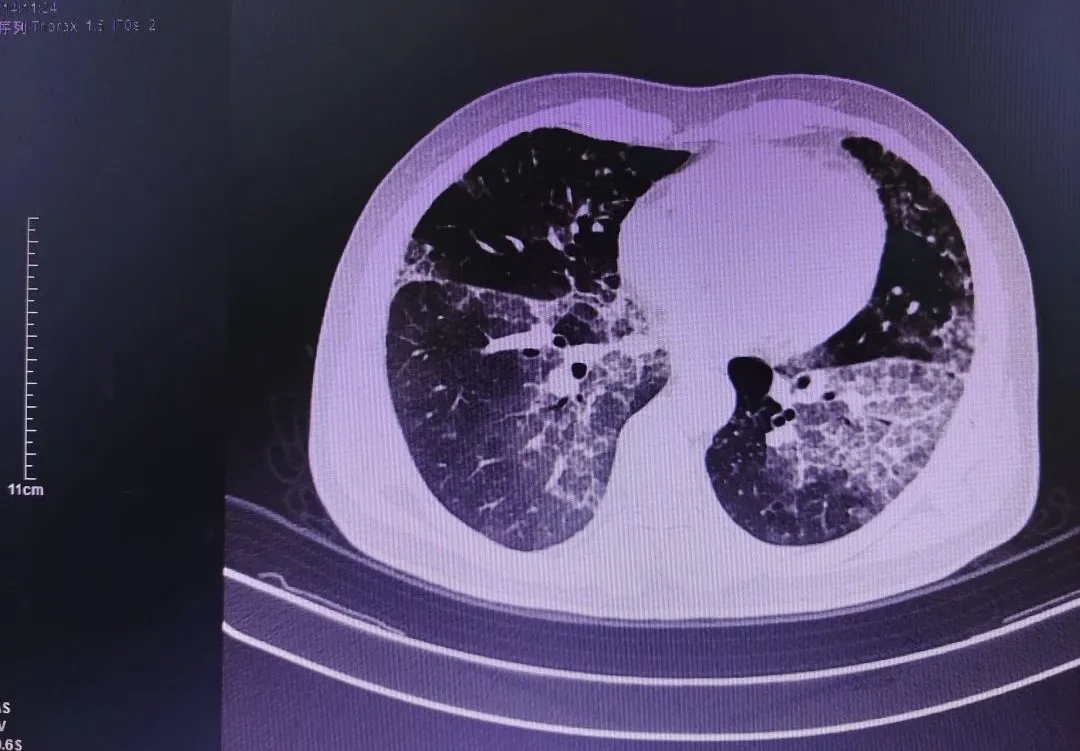

图1为入院时CT 图2为灌洗、治疗后CT

第二步,确诊后,分次行无痛电子支气管镜分段支气管肺泡灌洗术。其后,进行了3次治疗灌洗,总容量达9000ml,肺泡灌洗液由最初的浑浊牛奶色逐渐清亮。胸部CT提示双肺弥漫性病变较前明显改善。